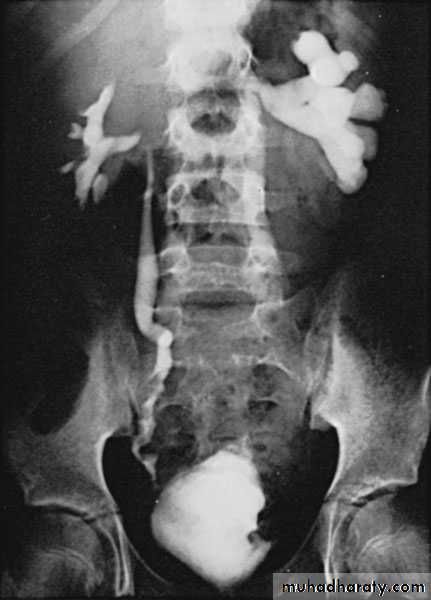

KUB: Renal calcification

IVU

CXR